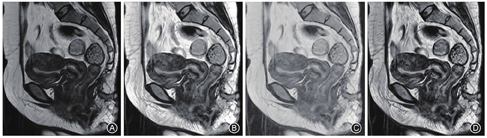

通过EXCEL软件随机化函数组合(INDIRECT+RANDABETWEEN),分别从上述两个数据库中选取200例患者。将每组200例患者按训练集、验证集和测试集以8∶1∶1的比例分配,均使用MRI仪(型号Optima 360 1.5 T,美国通用公司)检查,扫描参数见表1。肛管MRI序列包括T2平扫序列(轴位、冠状位和矢状位)和LAVA增强序列(轴位、冠状位和矢状位)。最后批量脱敏所有图像中的个人和医院信息数据,以DICOM格式保存。

算法构建的流程主要包括:(1)数据预处理。所有高分辨率MRI图像均接受图像质量增强,采用高斯去噪结合限制对比度自适应直方图均衡化算法提升图像对比度,使组织纹理更加清晰;(2)搭建DCNN,输入训练集的图像数据(CD肛瘘和腺源性肛瘘各160例,共78 321张MRI图像)进行模型训练,反向传播根据误差调整训练参数的值,迭代训练使最终的交叉熵损失最小,直至收敛;(3)根据验证集(CD肛瘘和腺源性肛瘘患者各20例,共9697张MRI图像)的结果选择最佳的训练模型。见图1、图2。